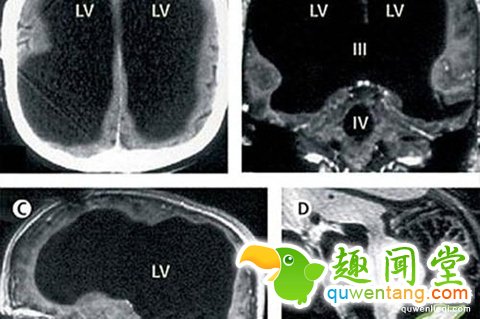

法国一名男子曾因腿部疼痛去医院检查,医生却找不出病根。在对其进行了全身体检后才发现,原来这名男子的腿疼是由脑部病变引起的,而该男子的大脑只剩下正常人大脑体积的一半都不到了。

这件事其实发生在2007年,近日由著名医学杂志《柳叶刀》披露。这名大脑神秘消失的男子当年44岁,医生在对其进行脑部检查后发现,他左右半脑上的额叶、顶叶、颞叶及枕叶都萎缩了。

在对这名男子的病史进行详细调查后发现,原来他童年时患有后天脑积水症。但在他14岁时,经历了分流术,随后的30年,这名男子和家人都以为完全康复了。但其实他的大脑还是在病变,最终,脑内的积水损坏了脑组织,导致其大脑50%至75%的部分都消失了。